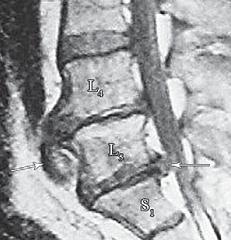

На МРТ № 18 наблюдаются грыжи межпозвонковых дисков в сегментах: — LIV-LV вентральной локализации с образованием каудального секвестра; при расположении межпозвонковой грыжи на один сегмент выше, «конфликт» с брюшной аортой был бы неизбежен; — LV-SI — дорсальная грыжа межпозвонкового диска, частично компенсированная спондилёзом МРТ № 19 ![]() МРТ № 20 ![]() На МРТ № 19 наблюдается дорсальная грыжа межпозвонкового диска шейного отдела позвоночника в сегменте СV-СVI с компрессией спинного мозга На МРТ № 20 наблюдается грыжа межпозвонкового диска шейного отдела позвоночника в сегменте CV—CVI и протрузия в сегменте CVI-CVII Замечу, что если грыжа межпозвонкового диска имеет достаточно большой размер и локализована в шейном отделе, то она способна вызвать не только соматические нарушения, но и даже психические расстройства. Причина кроется в сдавлении дурального мешка грыжей межпозвонкового диска (дуральный мешок — это герметичный соединительнотканный мешок, формируемый твёрдой мозговой оболочкой, в котором расположен спинной мозг). Как известно, спинной мозг не имеет болевых рецепторов. Однако вышеуказанная патология приводит к локальному устойчивому возбуждению определённых зон коры головного мозга. На субъективном уровне это может проявляться как постоянное чувство тревоги (так называемый «синдром ожидания»). Грыжи межпозвонковых дисков в грудном отделе позвоночника явление довольно редкое, но всё же наиболее опасное. Опасное потому, что эпидуральное пространство в грудном отделе позвоночника узкое по сравнению с другими отделами, в пределах всего 0,2–0,4 см по всей окружности дурального мешка (твёрдой оболочки спинного мозга). Поэтому даже небольшое грыжевое выпячивание может сдавить спинной мозг и вызвать тяжелейшие осложнения. Но, как уже говорилось, это явление в грудном отделе позвоночника редкое, поскольку высота межпозвонковых дисков довольно мала, всего около 3–5 мм, да и грудной отдел позвоночника менее подвижен по сравнению с другими отделами за счёт жёсткого рёберного каркаса, а значит, менее подвержен травматизации. МРТ № 21